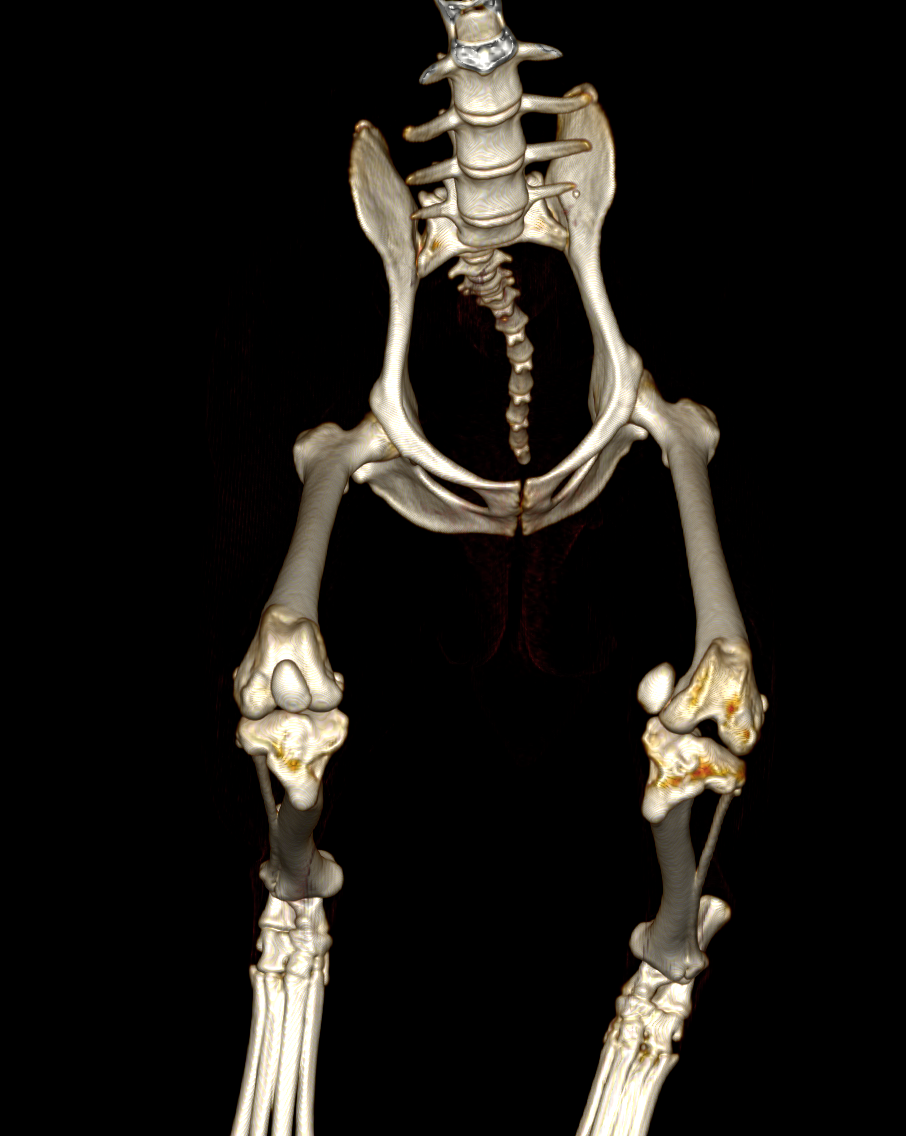

そのため、MPLグレード4の場合には手術の前にCT画像検査を実施し、大腿骨および脛骨と呼ばれる骨に変形がないかを確認します。レントゲンでも変形の評価はある程度可能ですが、3D的に変形していることが多いため、CT画像検査を実施しないと詳細がわからないことがほとんどです。

CT画像検査です。左のパテラ(向かって右側)は内側に大きく脱臼しています。この子の場合には大腿骨・脛骨共に大きな変形はないことがわかります。

この子は左右共にパテラが大きく脱臼しており、大腿骨・脛骨ともに大きく湾曲、回旋してしまっていました。

CT画像データから3Dプリンターで造形したものです。実際に手に取り手術を計画することができます。